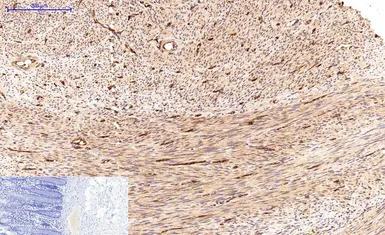

IHC-P analysis of mouse brain tissue using GTX34059 Survivin antibody [Mix]. Negative control (the lower left coner) was secondary antibody only.

Antigen retrieval : Sodium citrate pH6.0 was used for antibody retrieval (>98ºC, 20min)

Dilution : 1:200